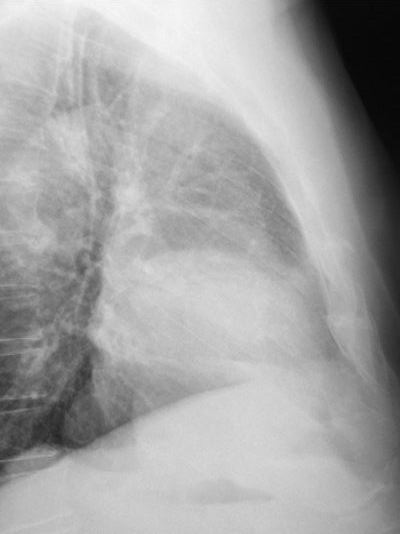

Fibrosis pulmonar. ICC.

Neumonia basal derecha.

Neumonía basal derecha.

Atelectasia lóbulo medio.

TBC pulmonar antigua

Tumoración mediastínica

Condensación en base izquierda.

Neumonía basal.